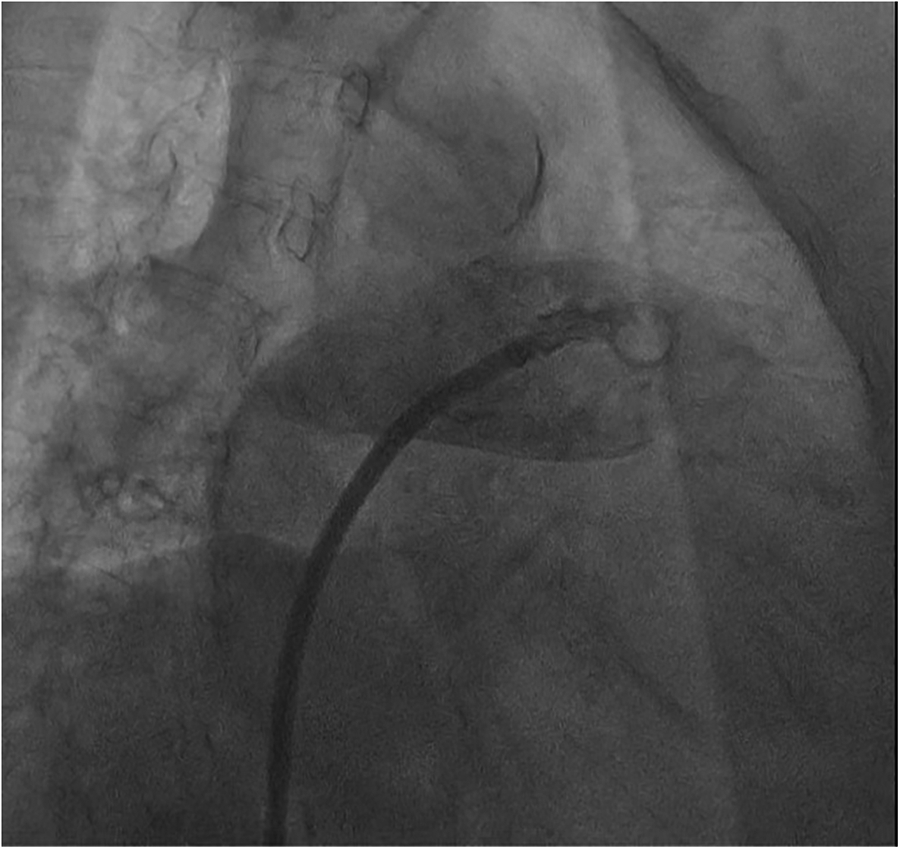

The procedure was performed under digital subtraction angiography (DSA) guidance, with puncture of the right femoral vein, placement of a 6F sheath, and transseptal puncture using a catheter in the conventional manner. Afterwards, we promptly advanced the transseptal sheath and encountered difficulty in accessing the left superior pulmonary vein with the guidewire, while contrast injection indicated visualization of the pulmonary artery (Figure 2).

Figure 2

Angiography shows brisk contrast extravasation into the pulmonary artery space.